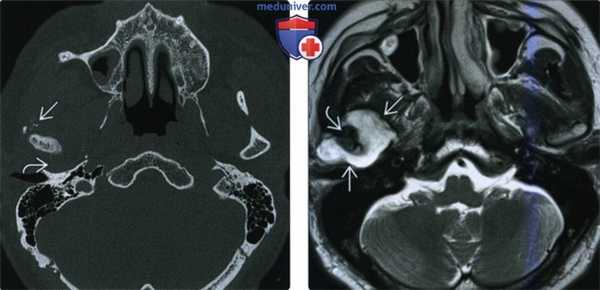

(Слева) КТ в костном окне, аксиальная проекция. Типичная хондросаркома височно-нижнечелюстного сустава низкой степени злокачественности. Определяются небольшие кальцификаты дистрофической природы (либо кальцифицированный матрикс самого образования) и обширная деарукция/ремоделирова -ние суставной ямки.

(Справа) MPT Т2ВИ в аксиальной проекции, тот же пациент. Определяется дольчатое гиперинтенсивное образование с четкими контурами, которое окружает мыщелок нижней челюсти.

(Слева) На корональной КТ с КУ визуализируется обызвествленная опухоль в жевательном пространаве, распроараняющаяся через основание черепа. Картина обызвеавления характерна для высокодифференцированной хондросаркомы.

(Справа) На аксиальной MPT (Т1 ВИ) визуализируется опухоль с промежуточным сигналом вокруг ветви нижней челюсти справа. В данном случае картина хондросаркомы жевательного пространства неспецифична.